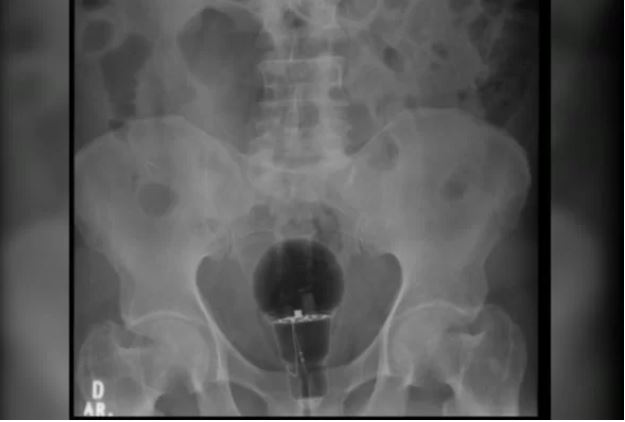

O médico disse que o paciente chegou com dores intensas e afirmou não saber do que se tratava, no entanto, exames de imagens mostraram que ele estava com uma lâmpada no reto.